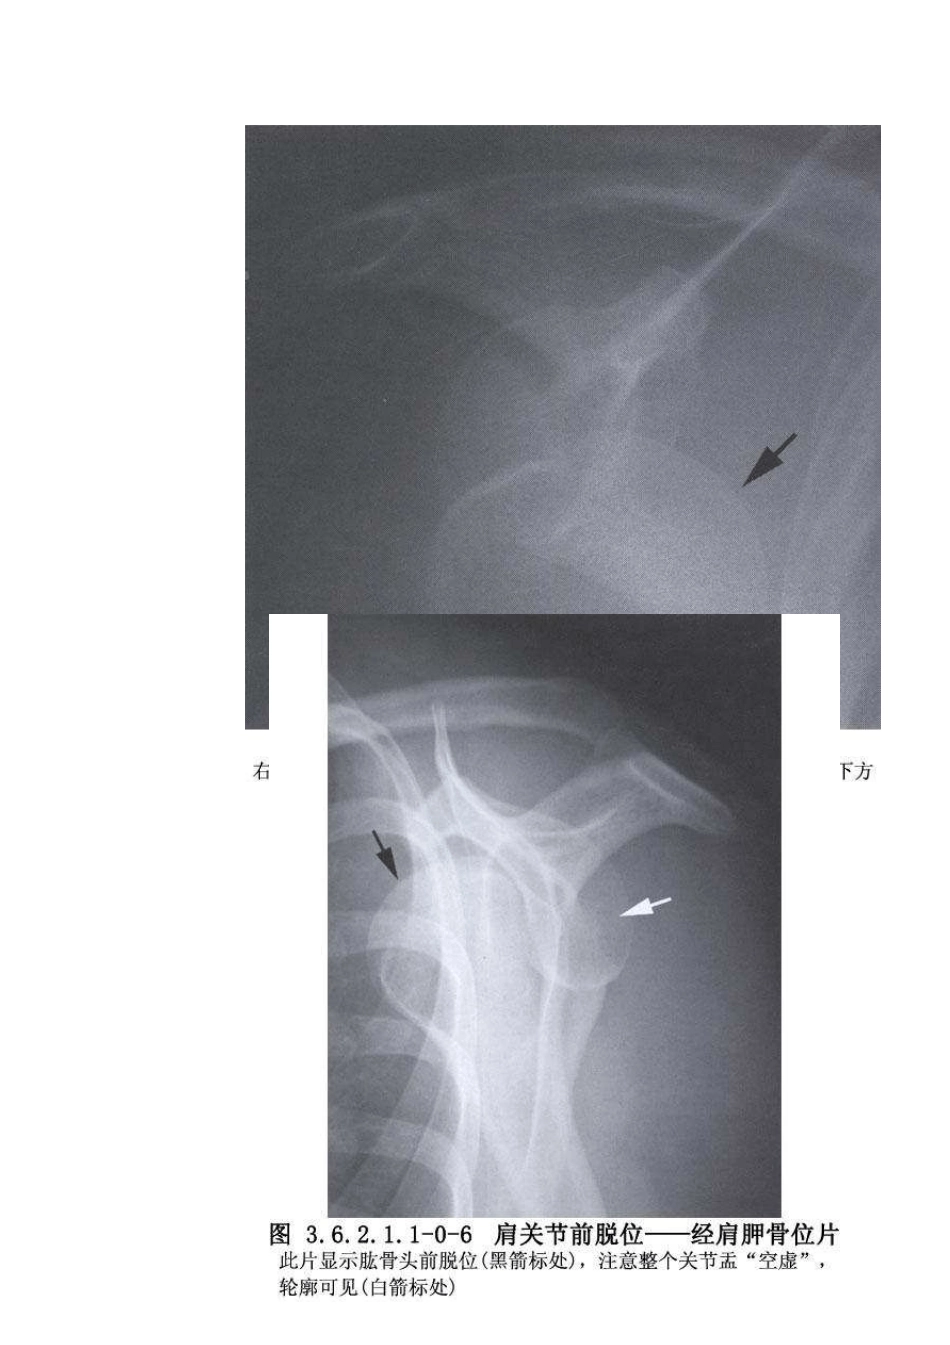

【编号】3.6.2.1.1 【手术名称】陈 旧 性 肩 关 节 前 脱 位 切 开 复 位 术 【英文名称】open reduction of old anterior dislocation of shoulder joint 【别名】open reduction of old anterior dislocation of shoulder 【ICD 编码】79.8101 【概述】 肩 关 节 脱 位 的 原 因 包 括 : ① 各 原 因 引 起 的 关 节 盂 前 缘 剥 离 。 ② 创 伤 引 起 的 关节 囊 韧 带 复 合 体 的 塑 型 改 变 。 ③ 先 天 性 关 节 囊 的 胶 原 缺 陷 引 起 的 关 节 囊 松 弛 。 ④外 伤 引 起 的 肱 骨 头 后 外 侧 面 嵌 插 骨 折 , 同 时 合 并 肩 关 节 盂 的 前 方 连 续 性 中 断 。 肩关 节 脱 位 相 关 解 剖 及 影 像 表 现 见 下 图 (图 3.6.2.1.1-0-1~ 3.6.2.1.1-0-8)。 肩关节脱位而未复位 3 周以上者,关节囊周围破裂的关节囊形成瘢痕组织,关节周围肌肉萎缩,骨折疏松出现,手法复位困难,应尽快切开复位。但老年病人 , 特 别 是 有 心 血 管 疾 病 者 , 脱 位 后 疼 痛 不 明 显 , 活 动 受 限 不 大 , 则 不 必 手 术 。 手 术 相 关 解 剖 见 下 图 (图 3.6.2.1.1-1~ 3.6.2.1.1-4)。 【适应证】 1.青壮年体力劳动者,脱位时间在1 个月以上,脱位关节已无松动的余地,手法整复失败者。 2.关节脱位合并有神经血管压迫症状,关节附近有明显骨痂形成,或大结节撕脱骨折,骨块卡于关节盂,以及脱位并发肱骨颈骨折者。 【禁忌证】 1.年老体弱,脱位已超过 3 个月,局部无疼痛,不伴有神经血管压迫症状者,不宜手术。 2.壮年病人,脱位在 3 个月以上。但关节功能尚可,肩外展可达 70°以上者,不宜手术。 【术前准备】 【麻醉与体位】 1.全身麻醉。 2.仰卧位,术侧肩后垫砂枕抬高。先使病人侧斜卧位,待颈肩胸背部皮肤灭菌并铺好无菌单后改为仰卧位。 【手术步骤】 1.切口与显露 肩关节前内侧切口,上起自锁骨外中 1/3 交界处,向外延至肩锁关节,向下沿三角肌前缘直至肱骨三角肌结节处。切开皮肤及皮下组织,认清三角肌及胸大肌间隙,顺三角肌纤维走向分离少许三角肌纤维,连同头静脉及胸大肌一并向内侧牵开,如显露尚嫌不足时,可将三角肌锁骨外 1/3 附着部距锁骨 1cm 处横行切断后将三角肌前...